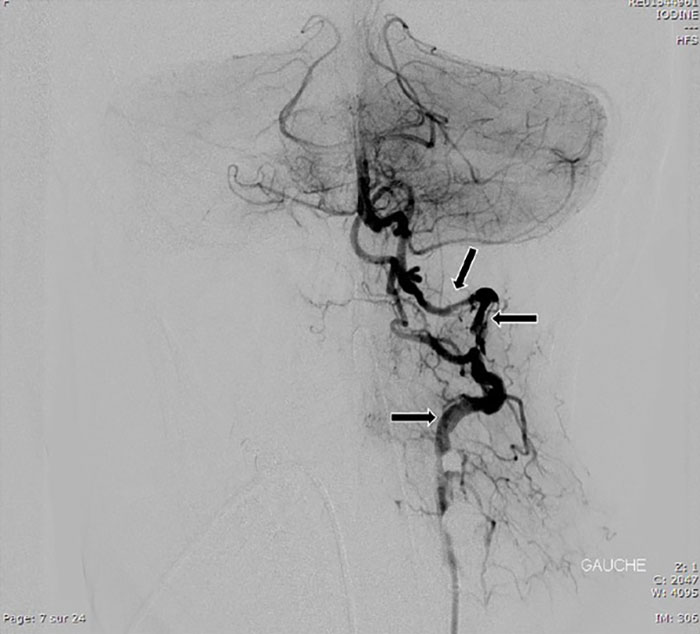

Image credits: National Library of Medicine